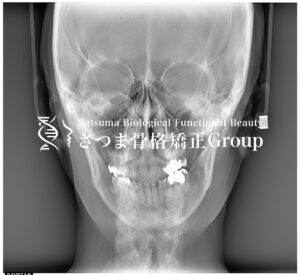

さつまではお顔の分析にあたり、セファロスタンドを使っています。 さつまでは主に口腔内から顎位や軟部組織に働きかけるお顔の施術を行いますので、まず通常の撮影した画像を参考に外形的な特徴を見ています。 バランスの良い美しいお […]

スタッフブログ, 渋谷院 院長 奥野さつまではお顔の分析にあたり、セファロスタンドを使っています。 さつまでは主に口腔内から顎位や軟部組織に働きかけるお顔の施術を行いますので、まず通常の撮影した画像を参考に外形的な特徴を見ています。 バランスの良い美しいお […]